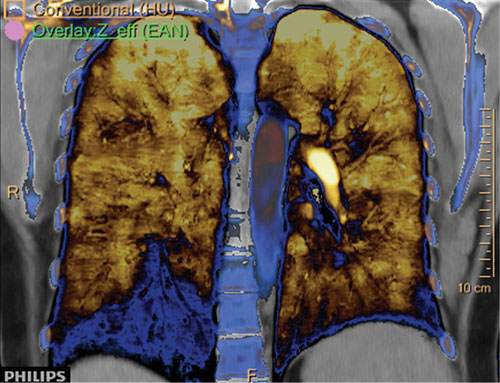

Effective Z.

A low dose computed tomography (CT) pulmonary artery angiography examination was performed using the IQon Spectral CT, with subsequent spectral data review and analysis.

The iodine and effective Z images demonstrate iodine perfusion defects in the right lower lobe that correlate to the filling defects in the conventional 120 kVp images. These findings confirm the differential diagnosis of a pulmonary embolus.